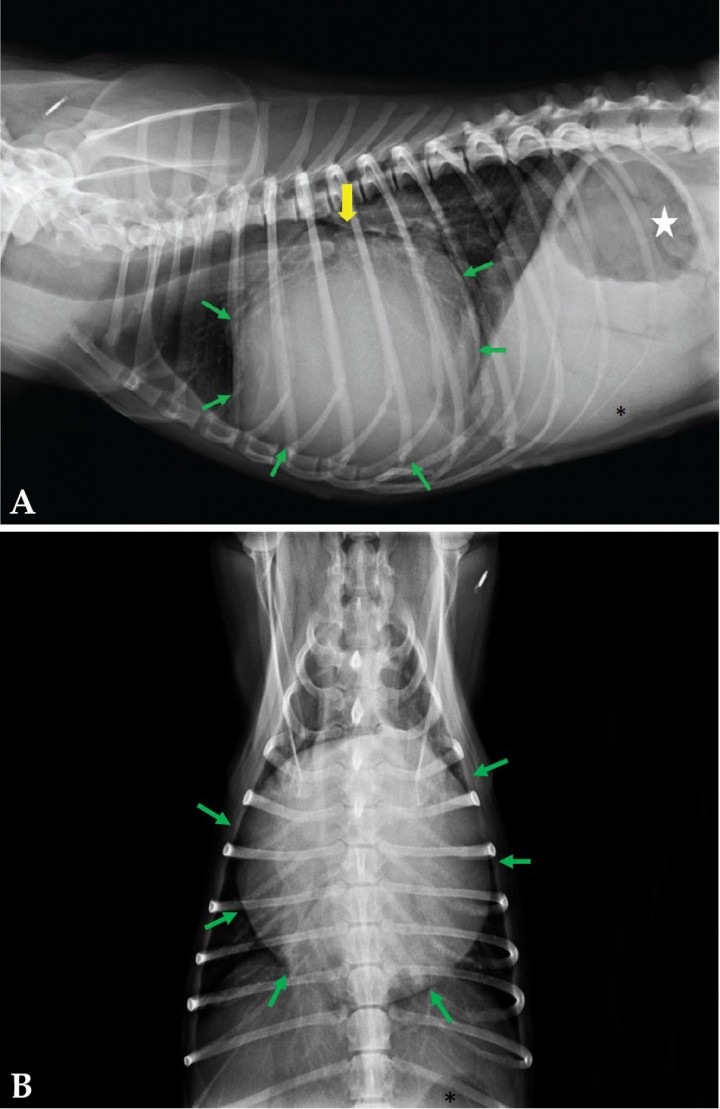

La silueta cardiaca se observa aumentada de tamaño (VHS=13,5, rango normal: 9,7±0,5), con bordes redondeados y aspecto globoide (Fig. 2), pérdida de definición de las estructuras cardiacas, incluido el borde epicárdico, y desplazamiento dorsal de la tráquea (Fig. 2A). La parte de abdomen visible en la radiografía muestra una moderada hepatomegalia (Fig. 2A) y gas en el estómago (Fig. 2A).

<p>Mismas imágenes que en la Figura 1. (<strong>A</strong> y <strong>B</strong>) Las flechas verdes demarcan los bordes de la silueta cardiaca. (<strong>A</strong>) La flecha amarilla indica el desplazamiento dorsal de la tráquea a causa de la grave cardiomegalia. El asterisco señala el ángulo caudoventral del hígado que sobrepasa el aspecto caudal de las costillas. Estómago ligeramente dilatado con presencia de gas en su interior (estrella).</p>

Mismas imágenes que en la Figura 1. (A y B) Las flechas verdes demarcan los bordes de la silueta cardiaca. (A) La flecha amarilla indica el desplazamiento dorsal de la tráquea a causa de la grave cardiomegalia. El asterisco señala el ángulo caudoventral del hígado que sobrepasa el aspecto caudal de las costillas. Estómago ligeramente dilatado con presencia de gas en su interior (estrella).